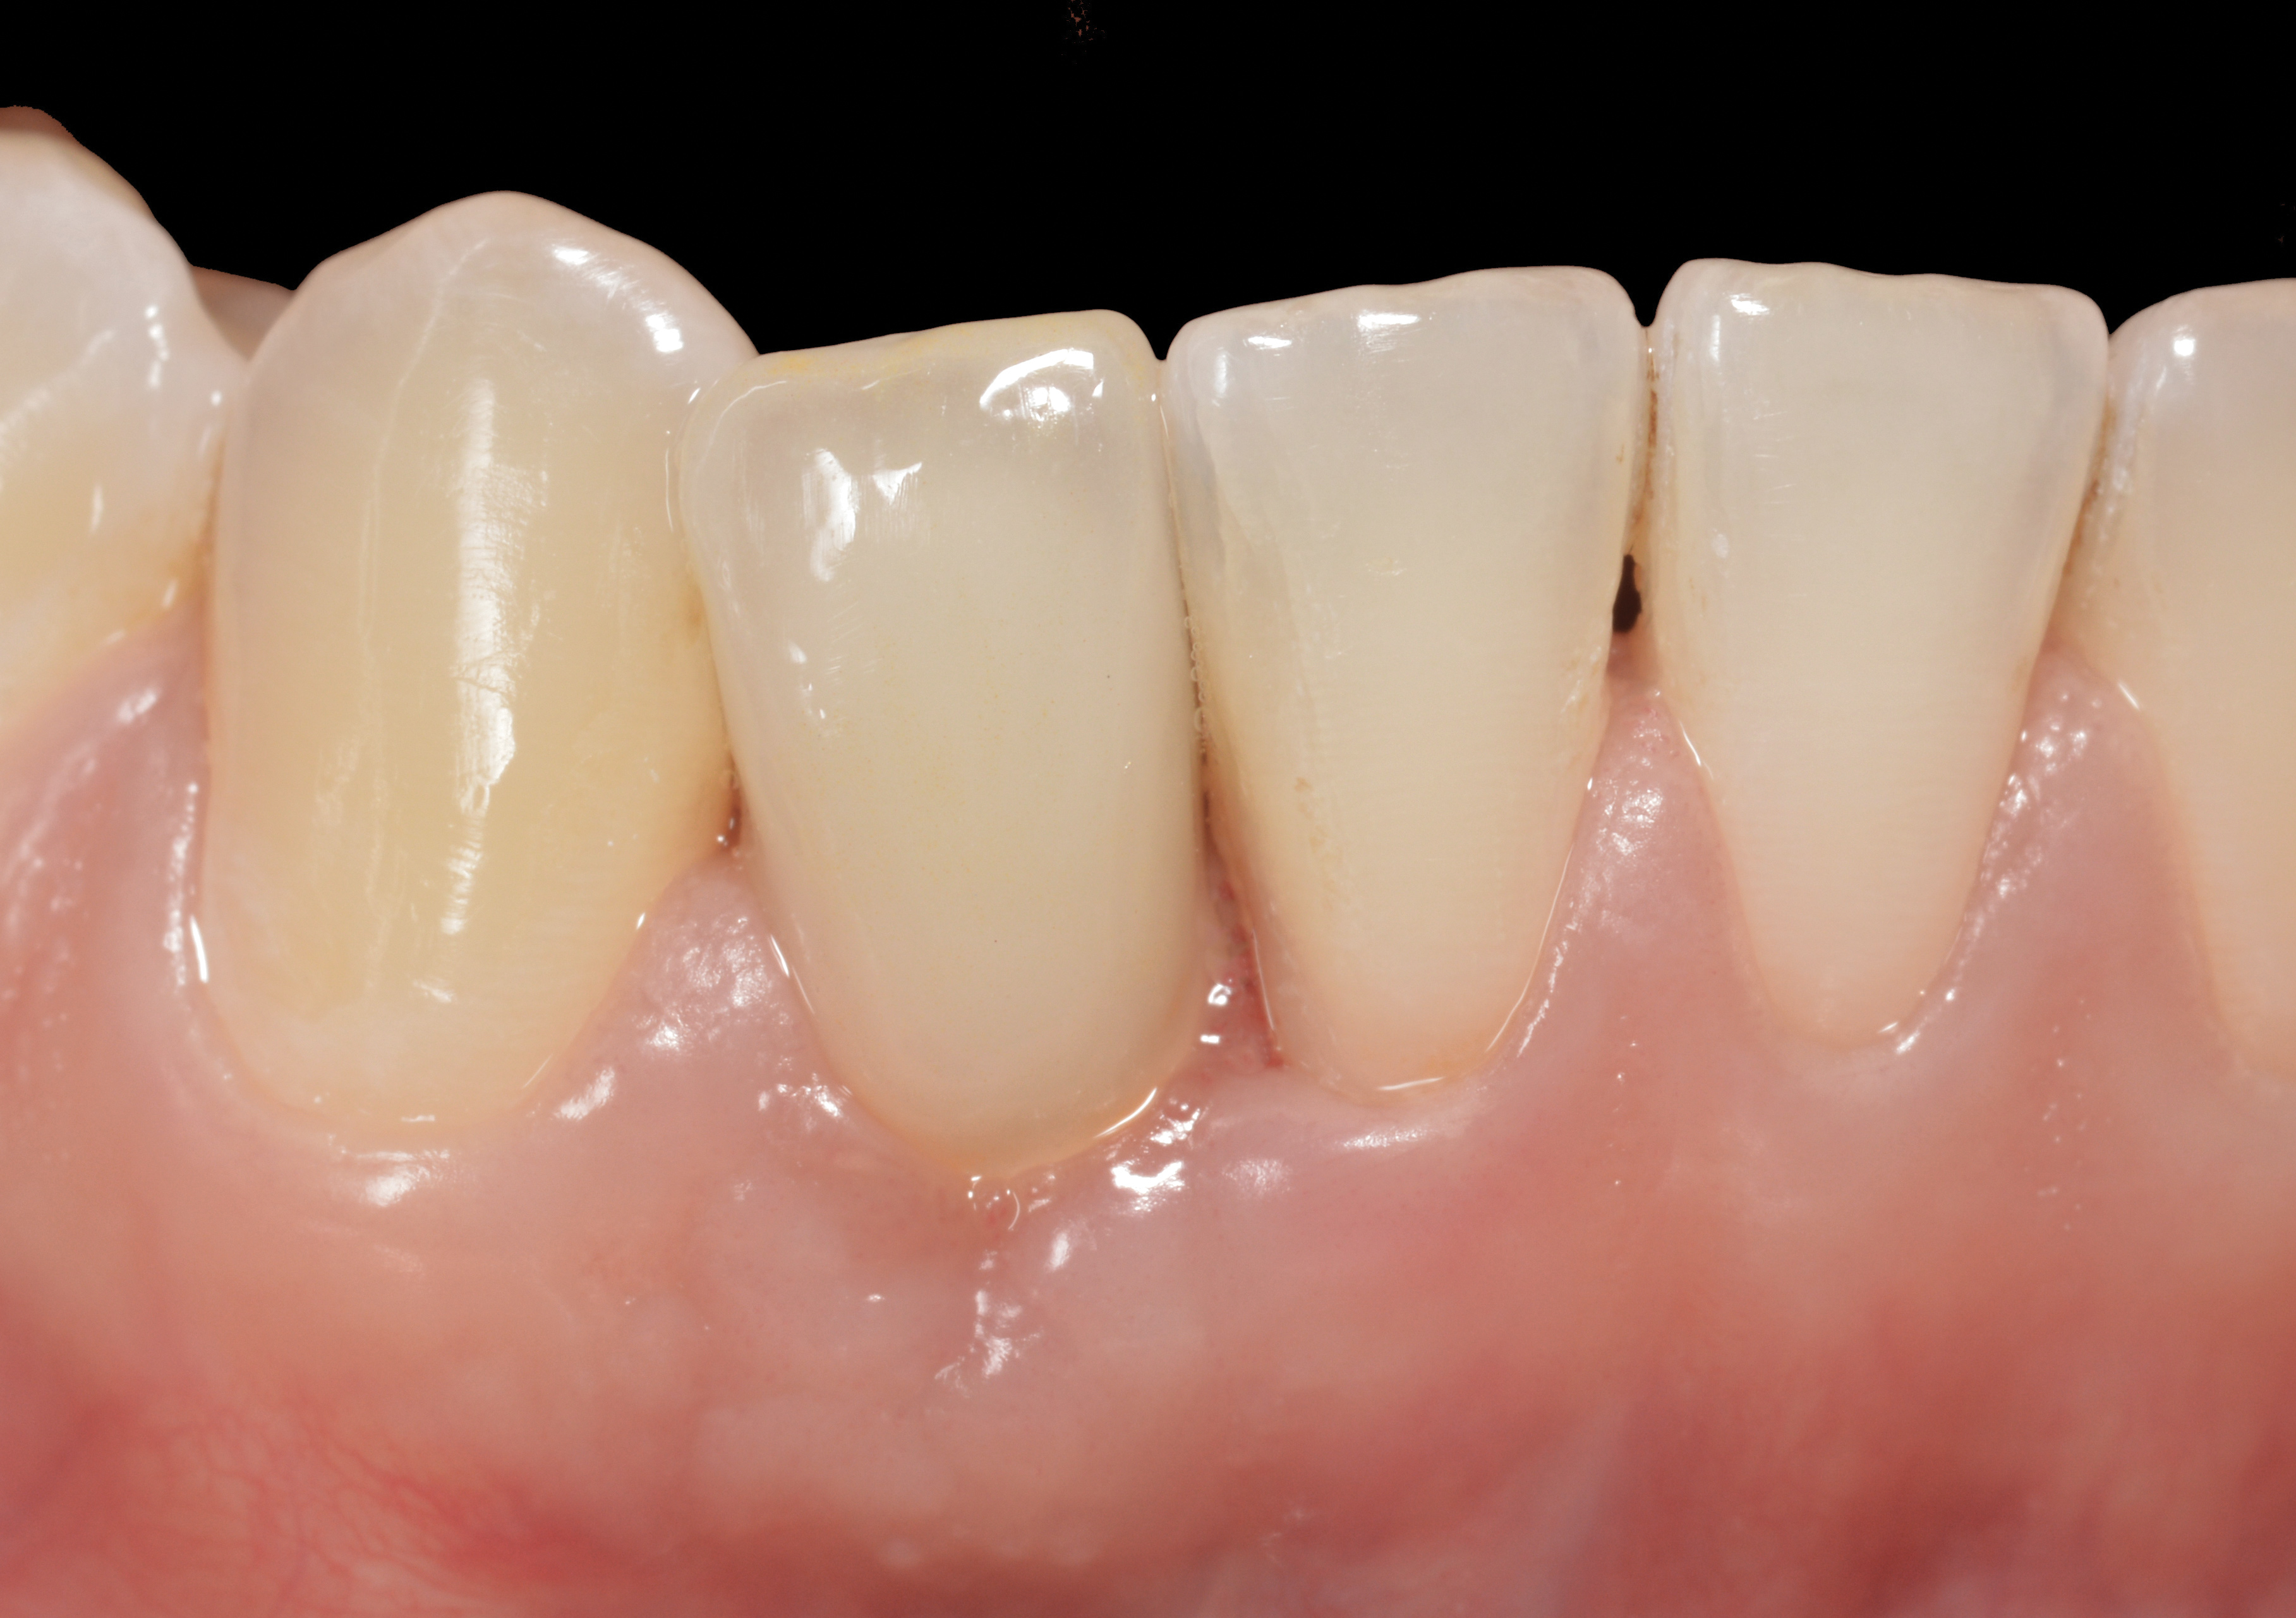

Fig 45. The definitive crown tooth No. 26 seated in place and provisionally cemented. The recession defect was eliminated with the removal and replacement of a new implant in the proper position.

Figure 45

The crown and screw-retained custom abutment were removed, and a surgical cover screw was placed into the implant, thereby allowing spontaneous gingival augmentation in situ (Figure 33 and Figure 34). Note that the lingual aspect of the implant site was significantly more coronal than the labial aspect, which was positive because the defect would be limited to a facial–lingual defect. A fixed RBR bridge was cemented on the adjacent teeth and used as a tooth-supported transitional provisional restoration (Figure 35). A few weeks were allotted to let the soft tissue heal and migrate around the cover screw (Figure 36) to see if there would be complete coverage, thereby allowing a soft-tissue augmentation procedure to be performed with primary flap closure as in clinical scenario No. 2. The major obstacle in achieving a positive tissue response was that the implant depth was also deficient because the implant–abutment connection was at the level of the free gingival margin. It was decided that the best treatment option would be to remove the implant. A high-powered reverse-torque device (Fixture Remover Kit, NeoBiotech, www.neobiotechus.com) was used to remove the implant atraumatically (Figure 38 through Figure 41). The implant socket was allowed to heal for several months not unlike an extracted tooth (Figure 42). A new implant was placed in a better position from both a restorative and esthetic perspective (Figure 43), and after a few months of healing, a new crown was made (Figure 44). A satisfactory functional and esthetic result was achieved (Figure 45 and Figure 46) without employing pink porcelain.